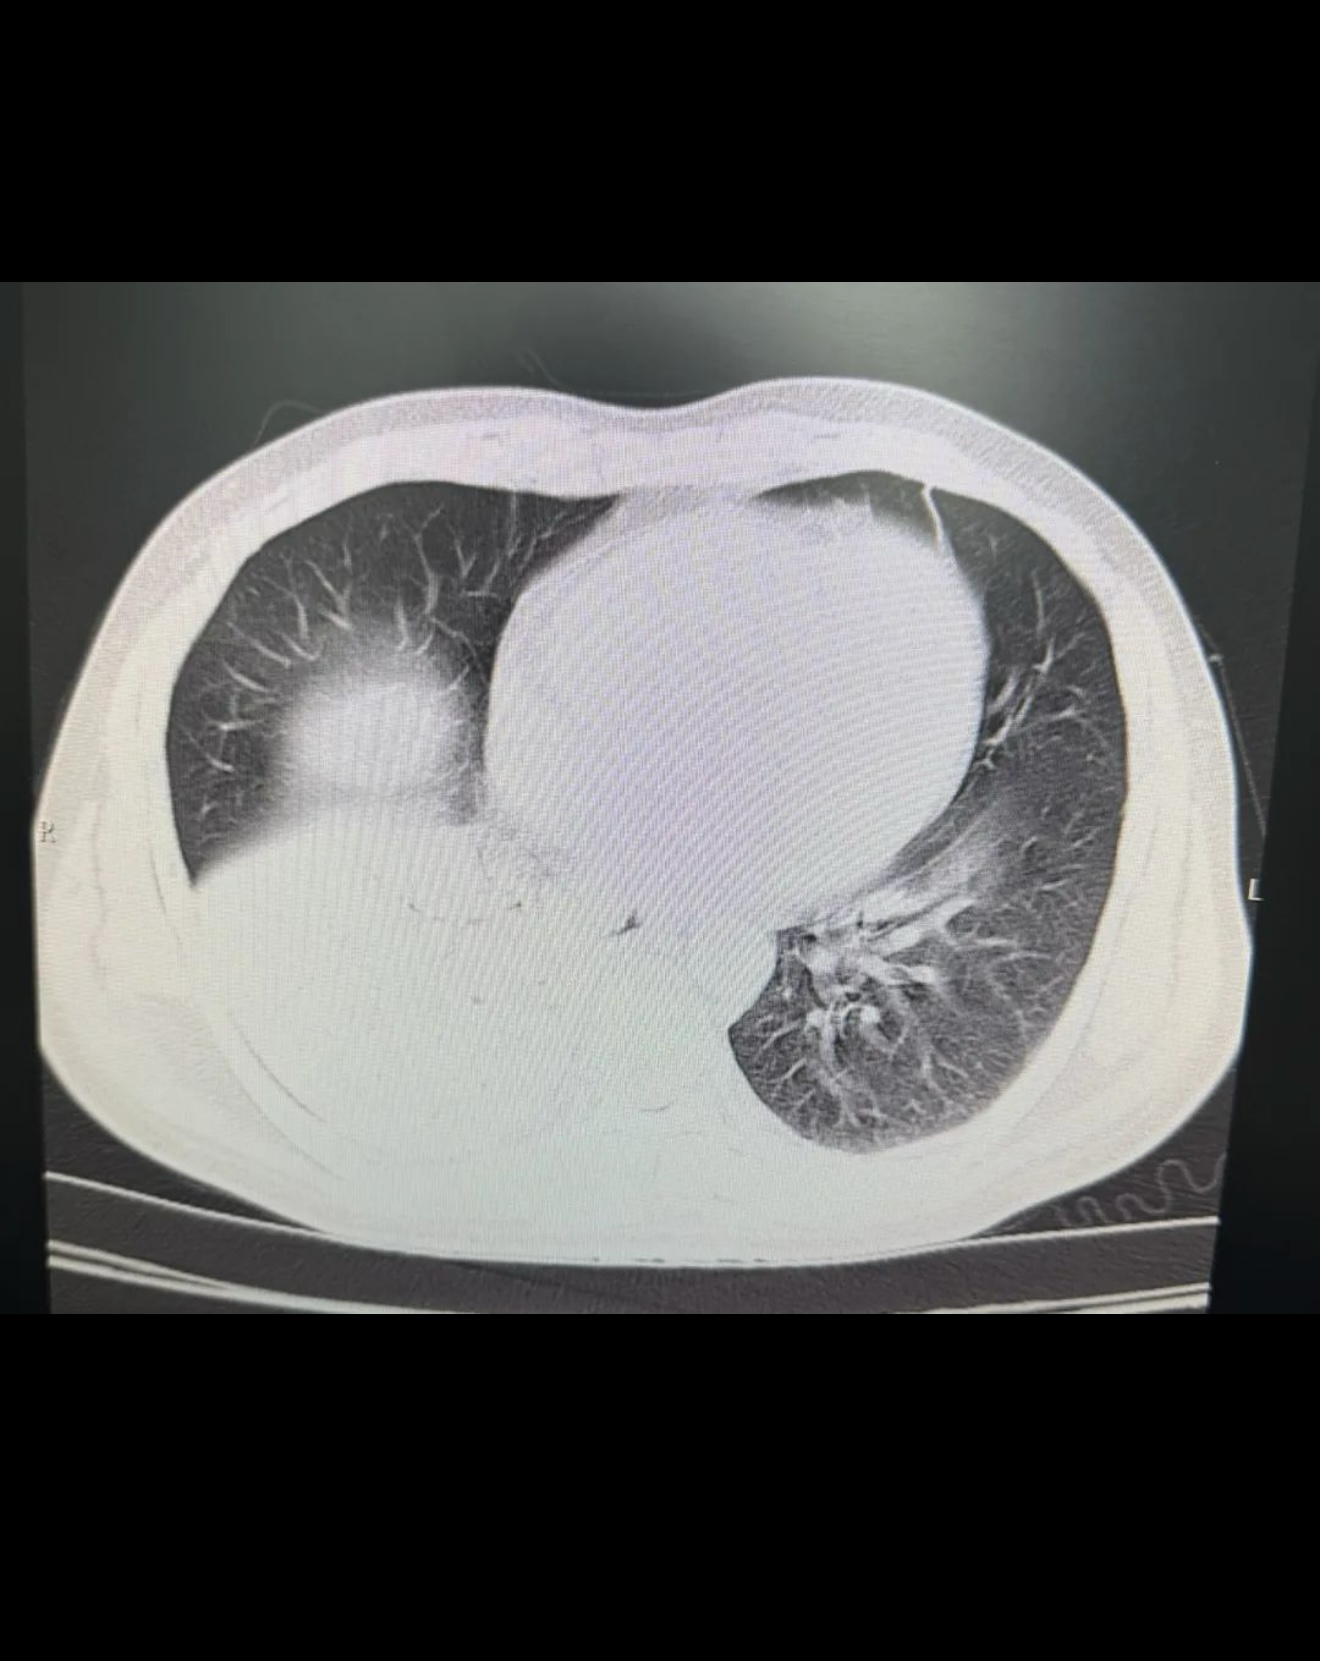

于07-06 胸部CT检查:右肺下叶实变伴不张,左肺下叶少许炎症。